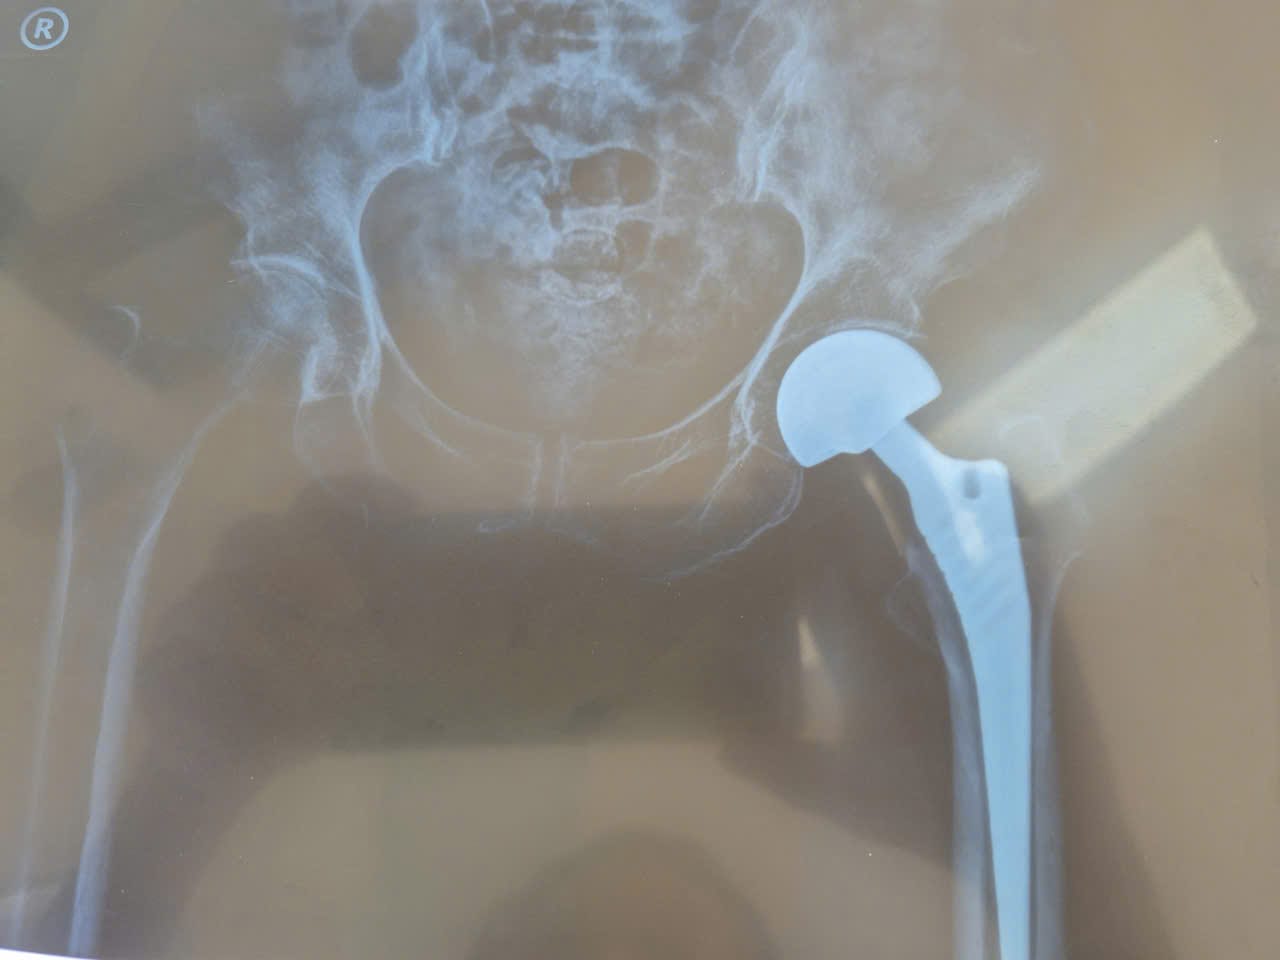

Trước bệnh cảnh trên tập thể khoa Ngoại nhận định đây là trường hợp gãy cổ xương đùi trái có chỉ định phẫu thuật để phục hồi chức năng vận động sớm, giảm đau cho bệnh nhân và tránh các biến chứng do gãy xương nằm lâu, hơn nữa bệnh nhân và gia đình có nguyện vọng tha thiết muốn phẫu thuật. Tuy nhiên BN rất cao tuổi, nguy cơ phẫu thuật cao, dễ xảy ra biến cố trong và sau mổ do đó cần sự phối hợp đa chuyên khoa. Một cuộc hội chẩn liên viện được tổ chức dưới sự chủ tọa BS Bành Quang Khải, Phó Giám đốc Trung tâm, bs Nguyễn Thành Phó khoa Gây mê hồi sức BVĐK TT tỉnh Gia Lai cùng bs khoa Ngoại, GMHS, HSTC của Trung tâm. Kết luận của hội đồng hội chẩn: Gãy cổ xương đùi trái Garden IV/ Viêm phổi-suy tim EF giảm-bệnh tim thiếu máu cục bộ có chỉ định thay khớp háng bán phần. Sau khi được điều trị nội khoa tích cực 3 ngày, BN được phẫu thuật với ekip gồm: BS Mang Đức Tiến Hoan, trưởng khoa Ngoại, phẫu thuật viên chính, BS Nguyễn Thành (BVĐKTT Gia Lai) gây mê chính cùng bs khoa Ngoại, Hồi sức cấp cứu. BN được thay khớp háng bán phần bipolar không xi măng. Cuộc phẫu thuật tiến hành trong vòng 90 phút, nhanh gọn chính xác, an toàn. Sau mổ được theo dõi sát tại khoa Hồi sức tích cực, từ ngày thứ 4, bệnh nhân bắt đầu tập đi với sự hỗ trợ của dụng cụ. Sau 8 ngày, Ekip phẫu thuật đánh giá tỉnh trạng lâm sàng ổn định, đã vận động đi lại chủ động với dụng cụ hỗ trợ, vết mổ lành, bệnh xuất viện trong niềm vui khôn xiết của bệnh nhân và gia đình.

Qua cas bệnh này cho thấy năng lực làm chủ kỹ thuật phẫu thuật thay khớp háng, sự phối hợp nhịp nhàng, hiệu quả giữa các chuyên khoa trong chẩn đoán, gây mê hồi sức, phẫu thuật và chăm sóc sau mổ, cùng với sự hỗ trợ chuyển giao kỹ thuật bài bản, đã góp phần mang lại thành công cho một ca phẫu thuật lớn trên bệnh nhân rất cao tuổi, nhiều bệnh nền tại tuyến y tế cơ sở.